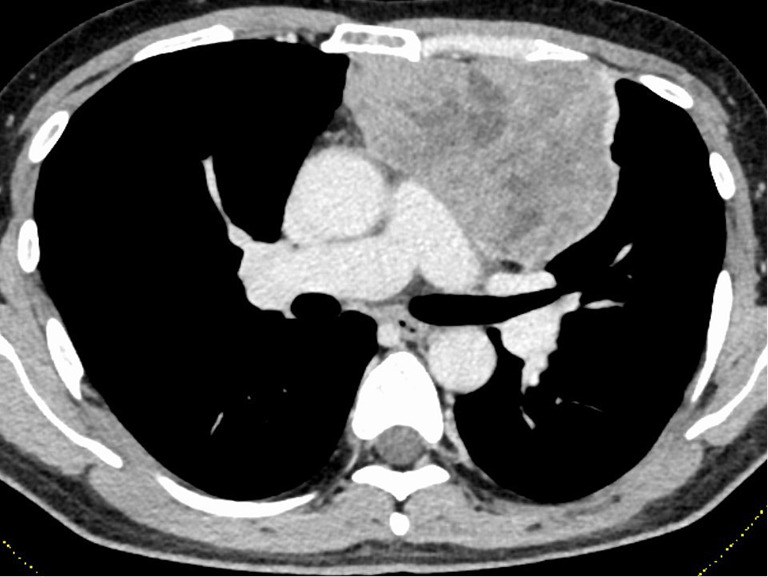

Case description: The first case was a male in his 50s who underwent surgery for Masaoka stage III type B3 thymoma. He experienced a loss of taste before surgery, which showed no improvement after surgery. Due to a MG crisis 44 days after surgery, the patient underwent intensive treatment with mechanical ventilation, steroid pulse therapy, and intravenous immunoglobulin (IVIG) therapy. The patient recovered taste when he started oral food intake after the treatment for the MG crisis (about 3 months after surgery). Despite the recovery of taste after steroid pulse therapy and IVIG therapy, taste disorder gradually worsened about 1 year and 9 months after surgery, resulting in an almost complete loss of sweet taste 2 years after surgery. The second case was a male in his 60s who underwent surgery for Masaoka stage II type B1 thymoma. He experienced loss of taste before surgery, which showed no improvement after surgery. Five years and two months after surgery, the patient was diagnosed with a MG crisis and underwent steroid pulse therapy. Along with improvements in MG symptoms, taste disorders gradually improved. After 6 years and 10 months of surgery, the patient is still alive without MG symptoms (only pyridostigmine, 180 mg/body/day), taste disorder, and thymoma recurrence.

Abstract Image